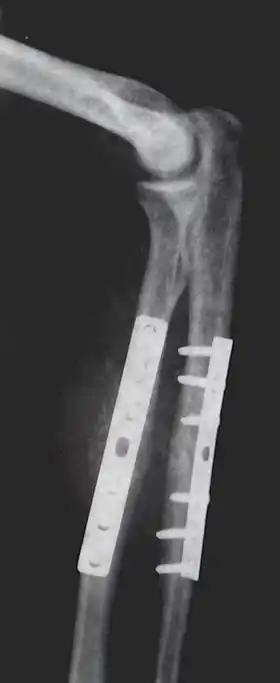

Closed Reduction Internal Fixation (CRIF) is reduction without any open surgery, followed by internal fixation. It appears to be an acceptable alternative in unstable distressed lateral condylar fractures of the humerus in children, but if fracture displacement after closed reduction exceeds 2 mm, open reduction and internal fixation is recommended.[4]